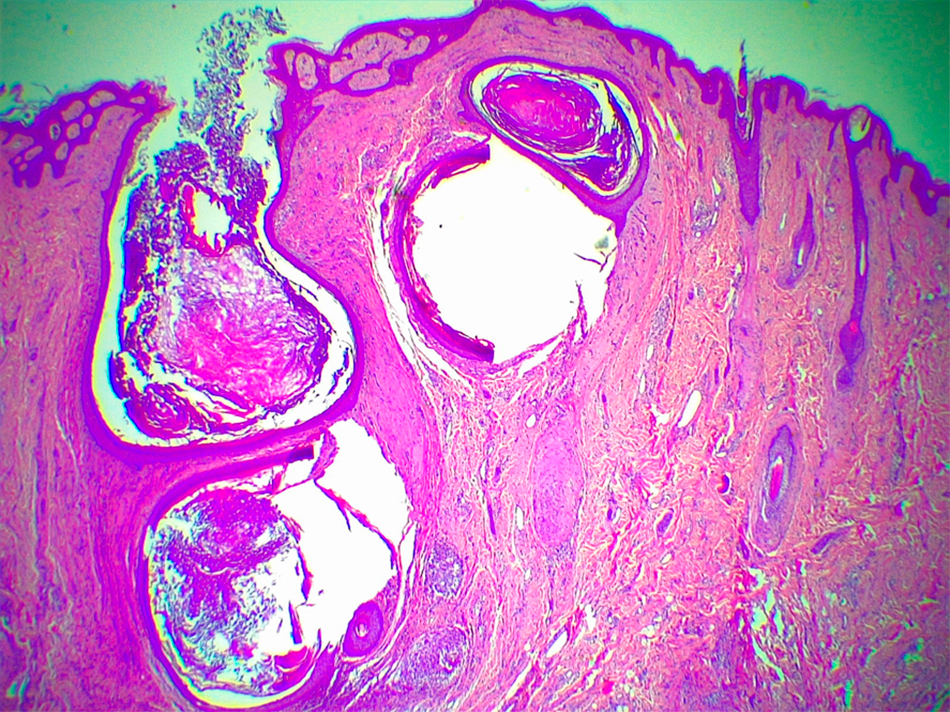

- Histología: Biopsia del flanco derecho con tinción de hematoxilina-eosina (Figuras 3 a 5) e inmunohistoquímica.